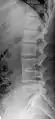

Short ribs at the first lumbar vertebra, which is thus a transitional vertebra, since lumbar vertebrae normally do not have ribs attached to them.

Transitional vertebrae have the characteristics of two types of vertebra. The condition usually involves the vertebral arch or transverse processes. It occurs at the cervicothoracic, thoracolumbar, or lumbosacral junction. For instance, the transverse process of the last cervical vertebra may resemble a rib. A transitional vertebra at the lumbosacral junction can cause arthritis, disk changes, or thecal sac compression. Back pain associated with lumbosacral transitional vertebrae (LSTV) is known as Bertolotti's syndrome. One study found that male German Shepherd Dogs with a lumbosacral transitional vertebra are at greater risk for cauda equina syndrome, which can cause rear limb weakness and incontinence.[10]